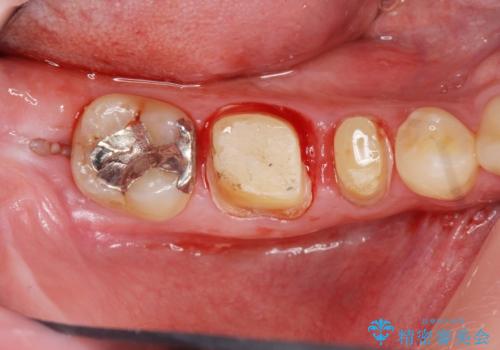

深い虫歯 セラミッククラウンの精度を高める歯周外科手術

マイクロスコープを用いた根管治療を行ったのち、深い虫歯に起因する歯ぐきの腫れ・出血を改善すべく歯周外科を行いました。

歯周組織が落ち着くのを待ち、セラミッククラウンで機能・審美性を改善します。